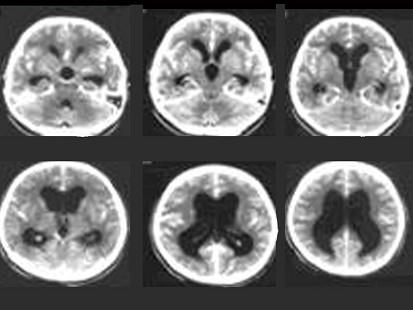

婴幼儿,女,头比一般孩子大,请结合影像图像选择最可能的诊断 ( )A、先天发育异常B、脑囊肿C、阻塞性脑积水D、交通性脑积水E、脑萎缩

问题 婴幼儿,女,头比一般孩子大,请结合影像图像选择最可能的诊断 ( )

选项 A、先天发育异常 B、脑囊肿 C、阻塞性脑积水 D、交通性脑积水 E、脑萎缩

答案 C